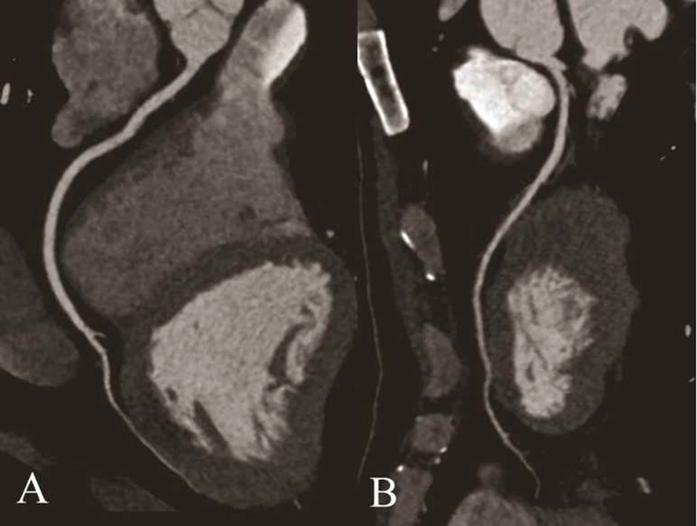

This study sought to compare the image quality and radiation dose of coronary computed tomography angiography (CCTA) from prospectively triggered 128-slice CT (128-MSCT) versus dual-source 64-slice CT (DSCT). The study was approved by the Medical Ethics Committee at Tongji Medical College of Huazhong University of Science and Technology. Eighty consecutive patients with stable heart rates lower than 70 bpm were enrolled. Forty patients were scanned with 128-MSCT, and the other 40 patients were scanned with DSCT. Two radiologists independently assessed the image quality in segments (diameter >1 mm) according to a three-point scale (1: excellent; 2: moderate; 3: insufficient). The CCTA radiation dose was calculated. Eighty patients with 526 segments in the 128-MSCT group and 544 segments in the DSCT group were evaluated. The image quality 1, 2 and 3 scores were 91.6%, 6.9% and 1.5%, respectively, for the 128-MSCT group and 97.6%, 1.7% and 0.7%, respectively, for the DSCT group, and there was a statistically significant inter-group difference (P ≤ 0.001). The effective doses were 3.0 mSv in the 128-MSCT group and 4.5 mSv in the DSCT group (P ≤ 0.001). Compared with DSCT, CCTA with prospectively triggered 128-MSCT had adequate image quality and a 33.3% lower radiation dose.

本研究旨在比较前瞻性触发 128 层 CT(128-MSCT)与双源 64 层 CT(DSCT)冠状动脉 CT 血管造影(CCTA)的图像质量和辐射剂量。该研究得到华中科技大学同济医学院医学伦理委员会的批准。连续纳入 80 例心率低于 70bpm 的稳定型患者。40 例患者行 128-MSCT 扫描,另 40 例患者行 DSCT 扫描。两名放射科医生独立根据三分制(1:优;2:良;3:差)对直径>1mm 的节段进行图像质量评估。计算 CCTA 辐射剂量。128-MSCT 组 80 例患者共 526 个节段,DSCT 组 80 例患者共 544 个节段。128-MSCT 组的图像质量评分 1、2 和 3 分别为 91.6%、6.9%和 1.5%,DSCT 组分别为 97.6%、1.7%和 0.7%,两组间差异有统计学意义(P≤0.001)。128-MSCT 组的有效剂量为 3.0mSv,DSCT 组为 4.5mSv(P≤0.001)。与 DSCT 相比,前瞻性触发 128-MSCT 的 CCTA 具有足够的图像质量,辐射剂量降低了 33.3%。